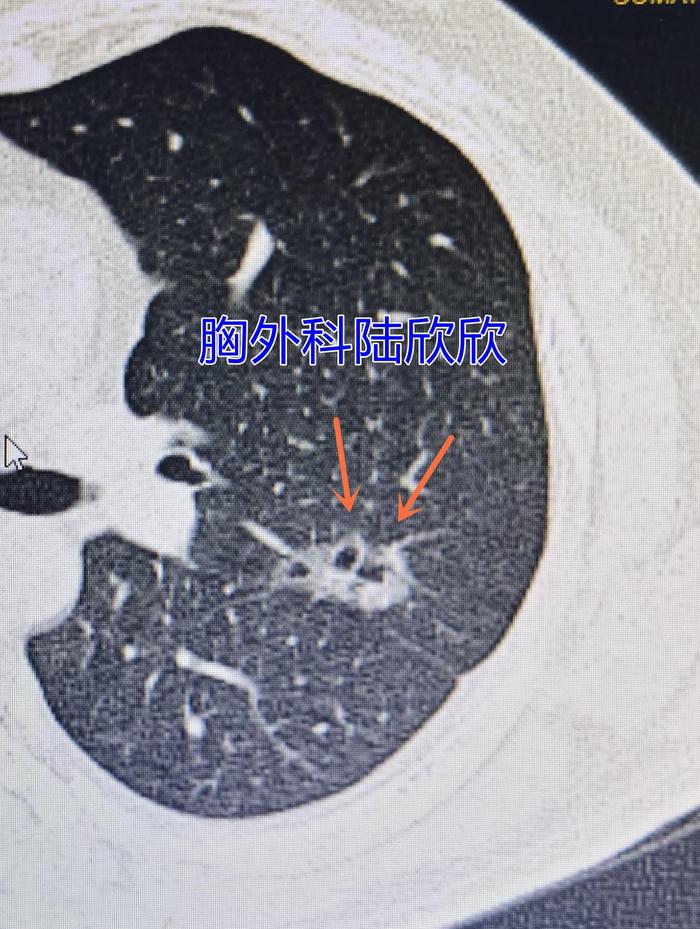

二、螺丝钉样磨玻璃结节。

上图可见左下肺胸膜下一个磨玻璃结节,长得很像一个螺丝钉。两个细箭头指示的是两个小空泡。大的粗的箭头指示的是背侧的一个磨玻璃结节。